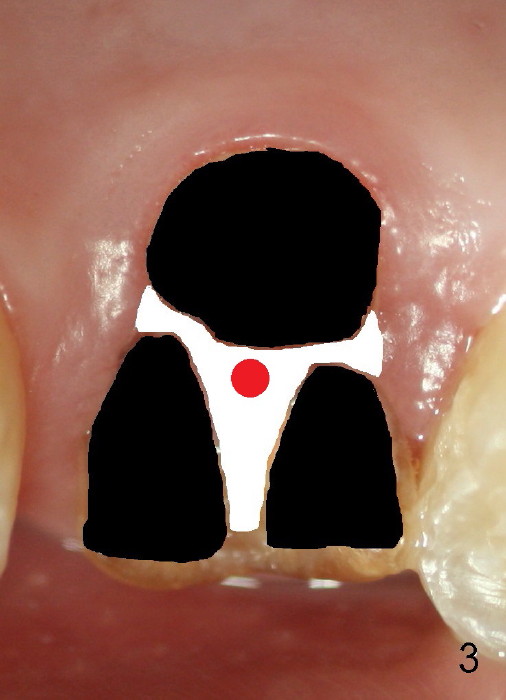

The 1st approach is used for the following case: a 46-year-old man with #14 (Fig.1). The root stumps are large and relatively close to each other (Fig.2 mirror view) so that when the roots are extracted (Fig.3 black), the septum is narrow (white). A 1.2 mm pilot drill penetrates the septum (red).